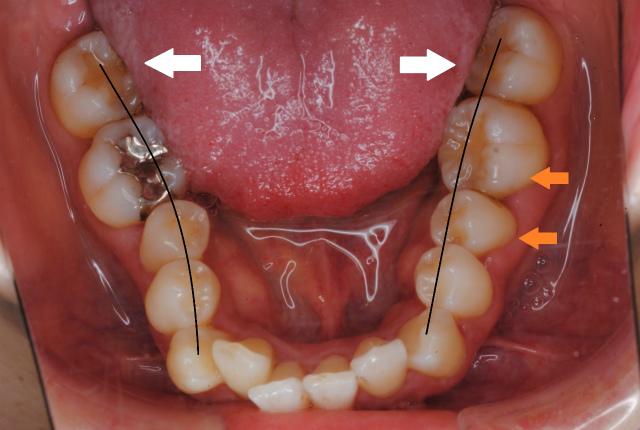

舌が下がると上あごは頬粘膜に押されて幅が狭くなり口蓋が深くなってしまう

舌の側面が臼歯に被さって歯並びに作用してしまう。左側臼歯が前方に傾斜している様子